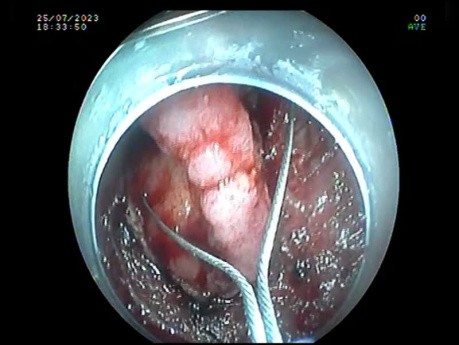

Endoskopowa dyssekcja podśluzówkowa (ESD) guza...

W filmie pokazano endoskopową dyssekcję podśluzówkową (ESD) guza typu LST-G odbytnicy rozciągającego się do linii zębatej. Zmianę sklasyfikowano jako LST-GH (homogenny)/ Paris IIa/ zwłóknienie F2. Zmianę...